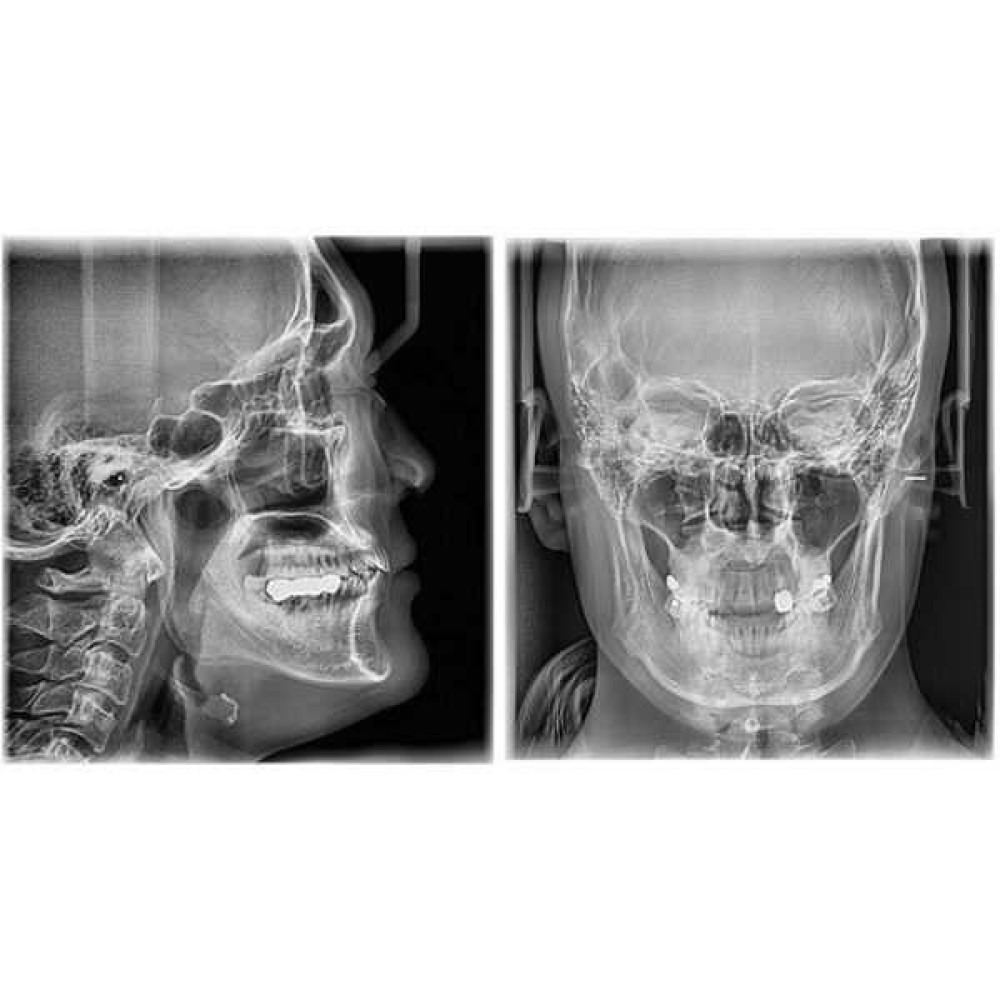

- PaX-i3D – Панорамный аппарат + Томограф

- PaX-i3D SC – Панорамный аппарат + Томограф + Цефалостат

- Функция Панорама+КЛKТ+Цеф